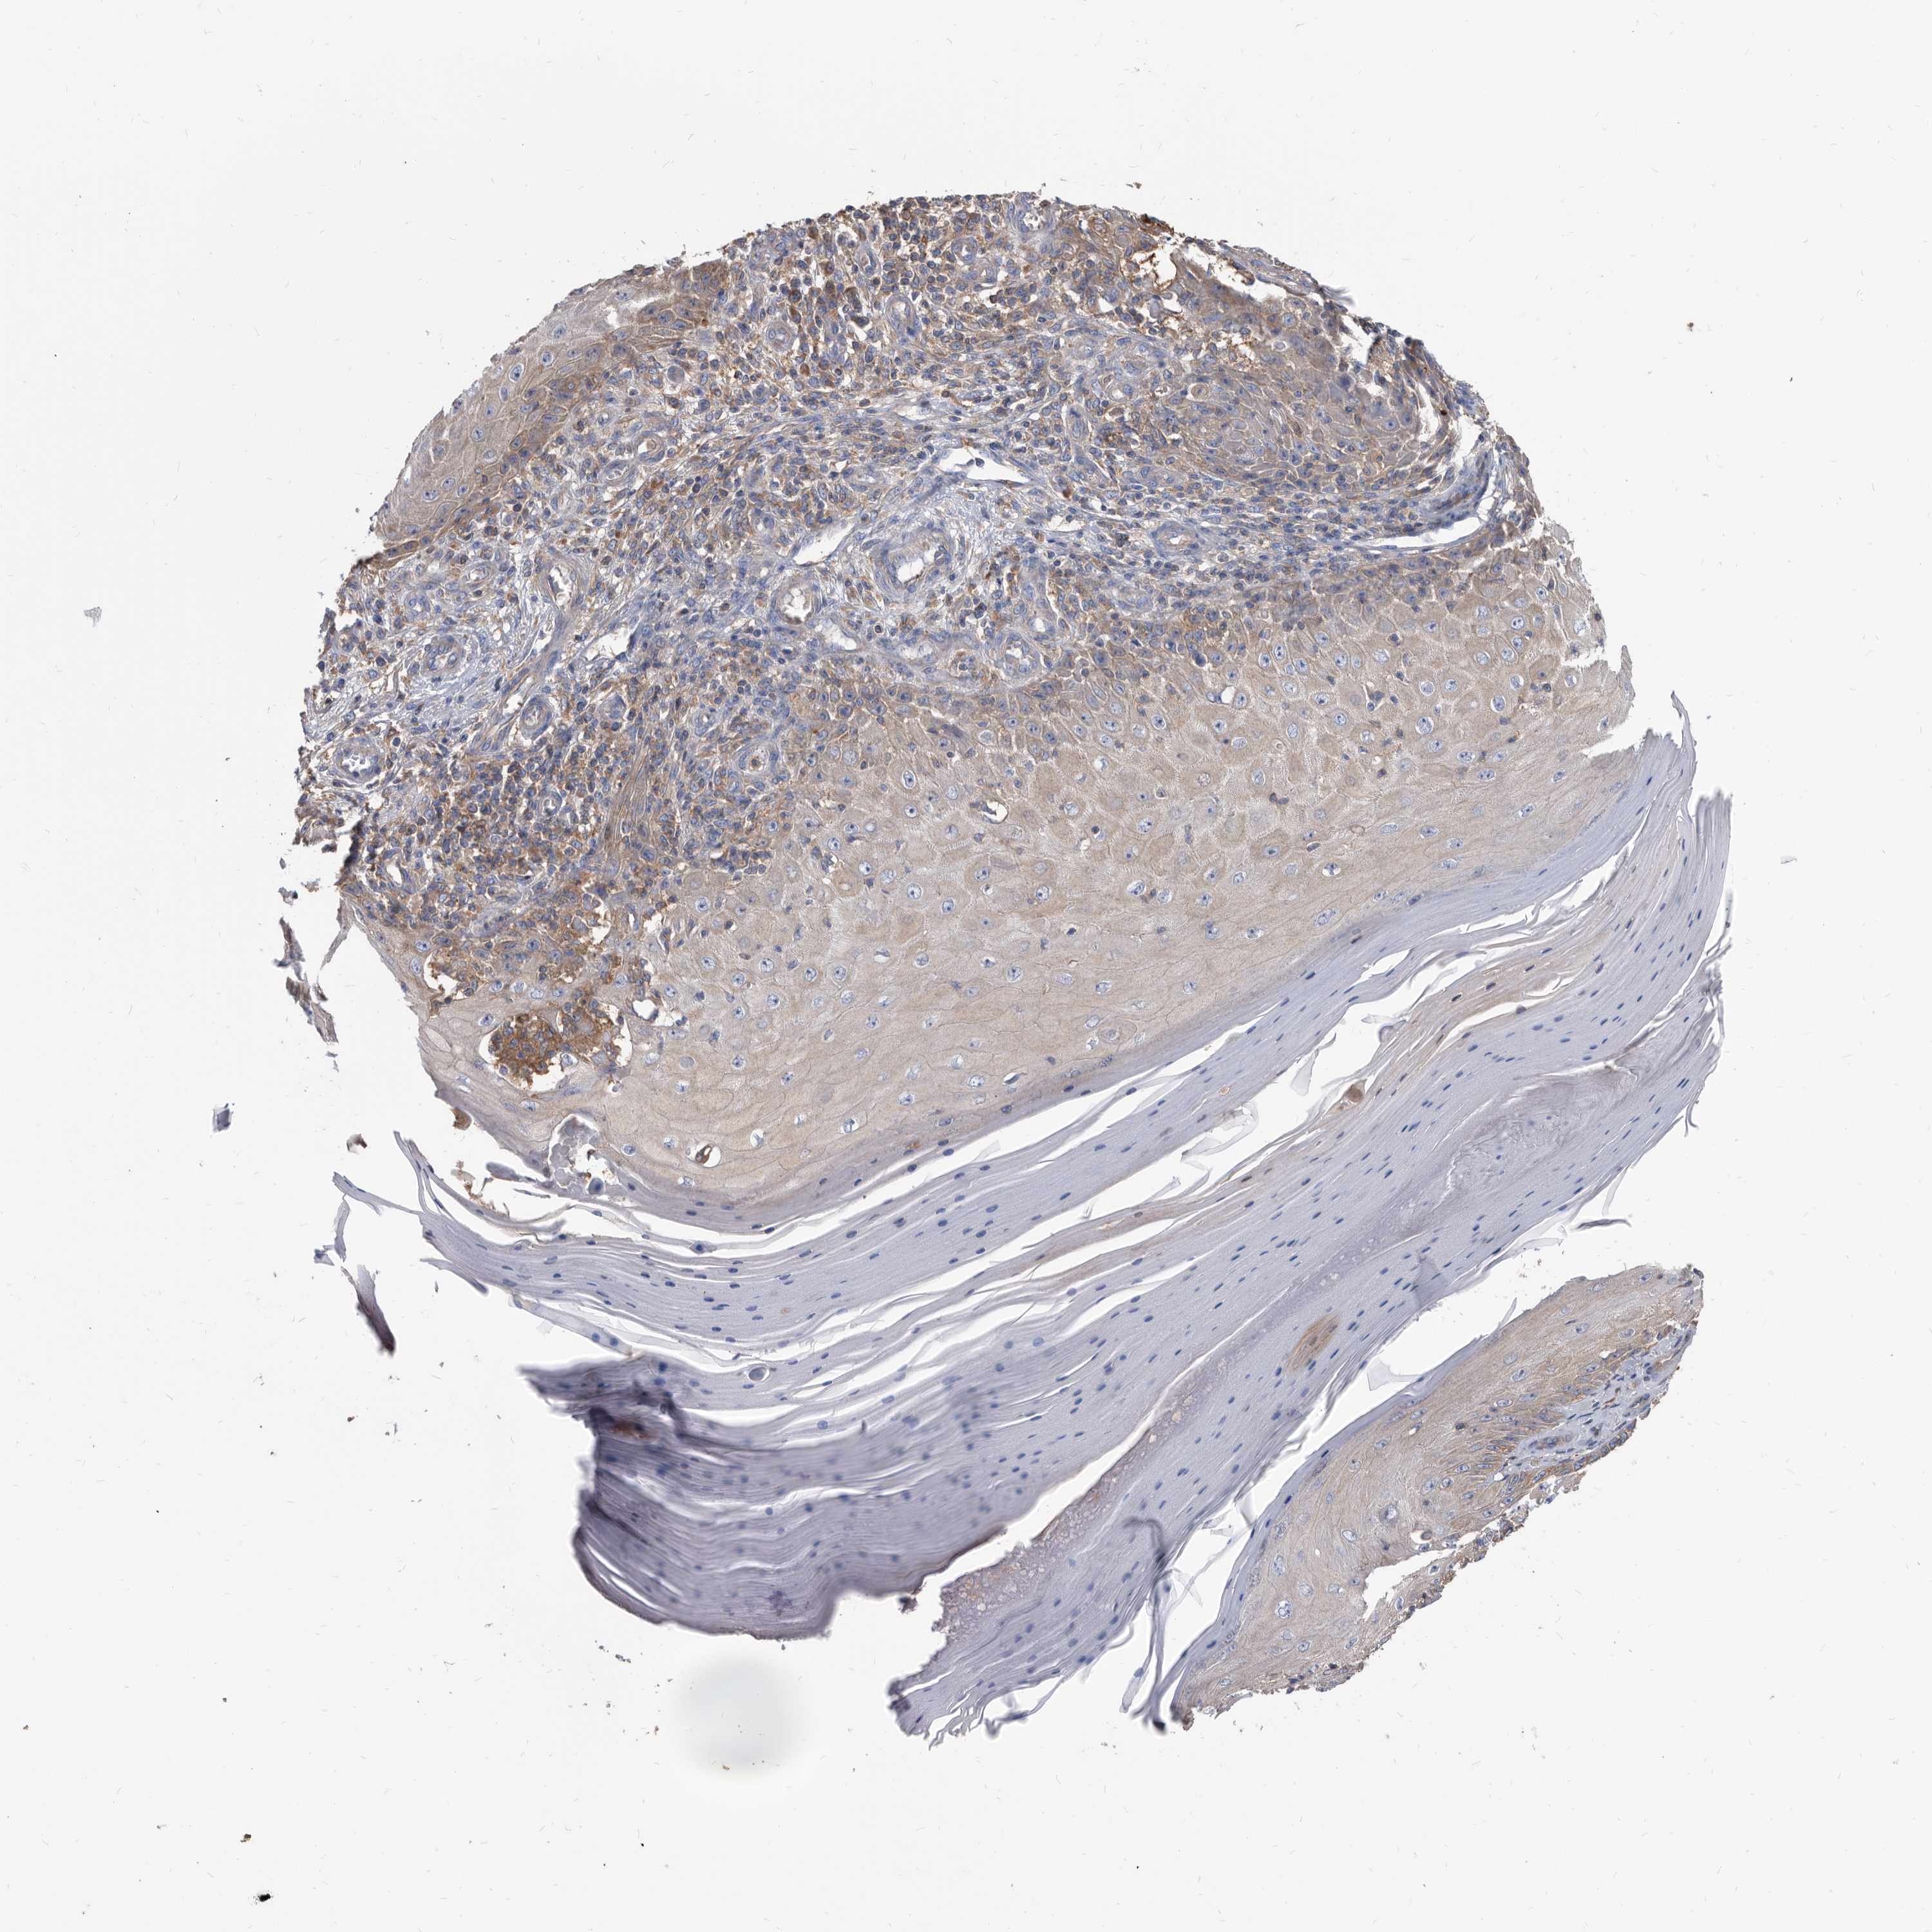

SKIN CANCER - Protein expressioni

A mouse-over function shows sample information and annotation data. Click on an image to view it in a full screen mode. Samples can be filtered based on level of antibody staining by selecting one or several of the following categories: high, medium, low and not detected. The assay and annotation is described here.

Antibody stainingi

Antibody staining in the annotated cell types in the current human tissue is reported as not detected, low, medium, or high, based on conventional immunohistochemistry profiling in selected tissues. This score is based on the combination of the staining intensity and fraction of stained cells.

Each image is clickable and will lead to virtual microscopy that enables deeper exploration of all samples and also displays staining intensity scores, fraction scores and subcellular localization as well as patient and tissue information for each sample.

Antibody HPA029700

Antibody HPA029701

Antibody HPA029702

Antibody HPA029703

Basal cell carcinoma